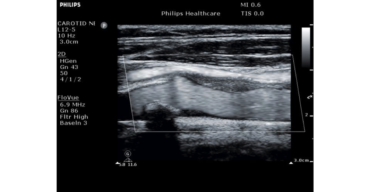

ecografo PHILIPS Clearvue 550

Progettato pensando alle esigenze di chi lo utilizza. Il sistema ecografico ClearVue 350 con tecnologia Active Array, che integra nel trasduttore le tecnologie fondamentali, garantisce una qualità eccellente delle immagini in uno strumento efficiente , affidabile ed estremamente compatto.

E’ facile perfezionare le prestazioni delle modalità bidimensionale e doppler con un solo clic, grazie all’ottimizzazione intelligente iScan che automaticamente regola e ottimizza gran parte dei parametri di uso frequente.